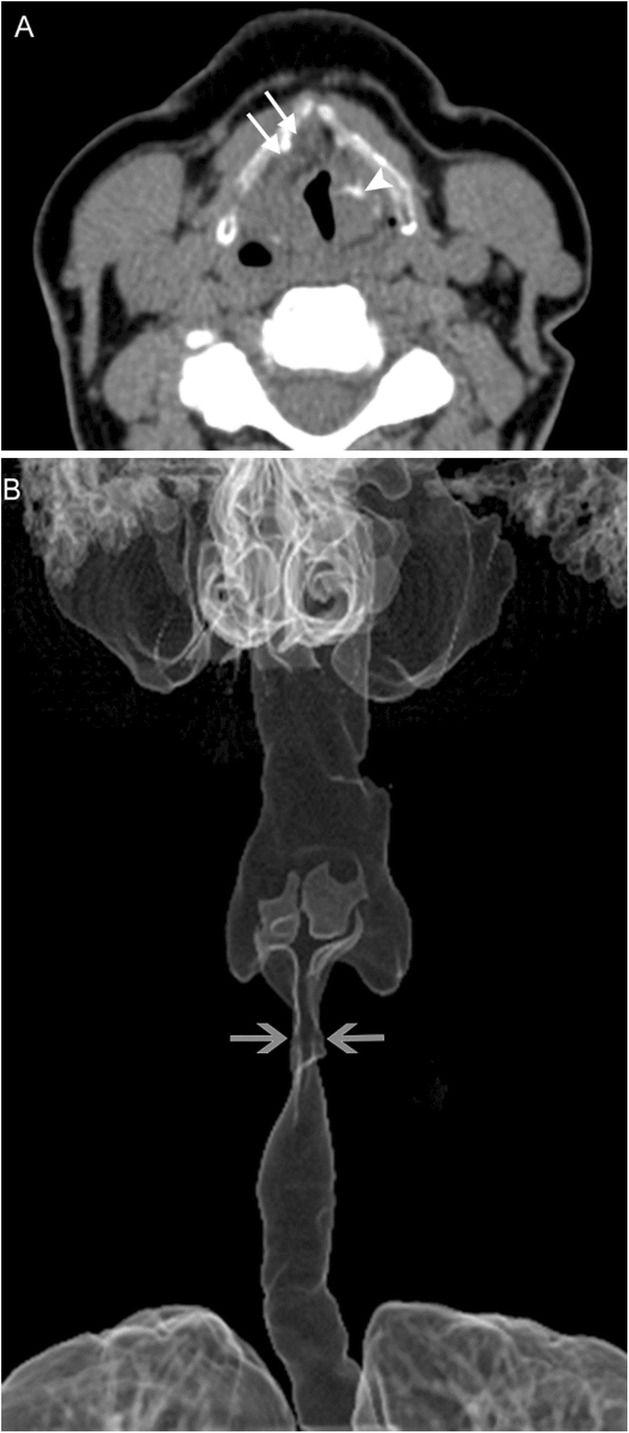

Amyloidosis is the extracellular deposition of a variety of fibrils that are composed of various low molecular weight subunits of proteins that are found normally in blood serum; this abnormal tissue is called amyloid. Laryngeal amyloidosis is a rare entity, accounting for only 1% of laryngeal masses [13, 14]. Amyloidosis is a slow progressive process that results in hoarseness due to tissue infiltration by amyloid, which alters the structure and mechanics of the vocal apparatus. Deposition in laryngeal tissue is most often a localized process, but systemic amyloidosis with laryngeal involvement is usually due to a monoclonal plasma cell dyscrasia. Imaging findings in amyloidosis are nonspecific and result from architectural distortion of laryngeal structures due to tissue infiltration (Fig. 9). Treatment consists of endoluminal microsurgical resection or debulking, and often requires multiple sessions due to extent and recurrence [15].

Fig. 9.

Laryngeal amyloidosis. A 69-year-old woman with recurrent laryngeal amyloidosis despite multiple interventions. Axial CT image (a) reveals marked soft tissue thickening of the laryngeal structures extending into the right pre/paraglottic space (white arrows) representing amyloid infiltration, and dystrophic calcification (white arrowhead) representing post-treatment change. The true vocal cords are not identifiable. 3D surface volume rendering (b) demonstrates marked narrowing of the glottic airway (gray arrows)